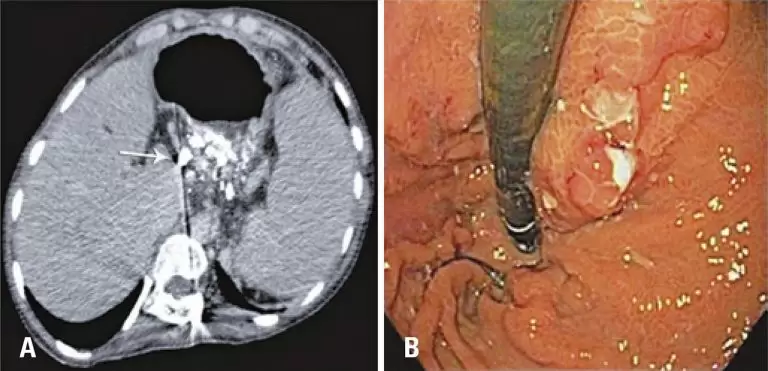

ABSTRACT Major liver resections require extensive margins. Occasionally, insufficient parenchyma is available after surgery to maintain liver function. In such cases, vascular embolization in the affected lobe is necessary to induce contralateral lobe hypertrophy. We present a case of embolization of the right portal and hepatic veins prior to intrahepatic cholangiocarcinoma resection. Embolization was performed because of insufficient residual parenchyma on imaging studies. The patient recovered well with no signs of liver failure, and remains in remission at 3 years […]